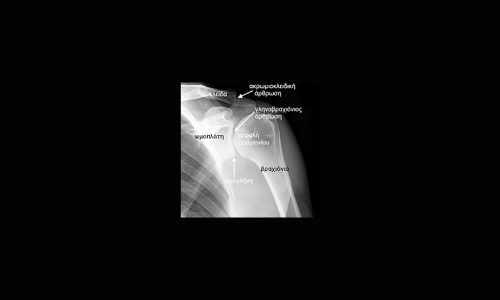

Πρόκειται για πάθηση της άρθρωσης του ώμου. Ο ώμος αποτελείται από τρία οστά, την κλείδα, την ωμοπλάτη και το βραχιόνιο οστό.

Ωμογλήνη είναι η αρθρική επιφάνεια της ωμοπλάτης, η επιφάνεια δηλαδή όπου “γλιστρά” η κεφαλή του βραχιονίου. Γύρω από αυτή βρίσκεται προσκολλημένος ο επιχείλιος χόνδρος (labrum), ο οποίος αυξάνει το εμβαδόν της ωμογλήνης και βαθαίνει ελαφρώς την υπόκοιλη επιφάνειά της, προσφέροντας αύξηση της σταθερότητας στην άρθρωση.